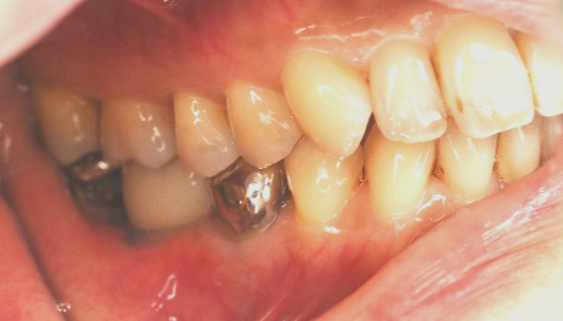

男性 Kさん 60代 (インプラント)

主訴

下の左右歯がないところに歯を入れたい。

治療内容

左右それぞれ3本歯がないところに2本ずつインプラントを埋入しました。

所感

上と下の歯の咬合接触がないすれ違い咬合です。上下義歯で対応するには最も難しいタイプの欠損状況です。治療開始前は、上下部分入れ歯が入っていましたが、入れ歯の安定が悪く、あちこちの歯茎に入れ歯が当たって痛く、満足に噛める状態ではありませんでした。上顎は、残ってる歯を活用するマグネット式総義歯を、下顎はインプラントを提案しました。上顎は、現在残っている歯の根管治療中です。上顎にマグネット式総義歯がはいれば、何でも食べられるようになります。

インプラント4本:¥363,000×4本=¥1,452,000(税込)

ポンティック2本:¥115,500×2本=¥231,000(税込)

合計:¥1,683,000(税込)

Before

▼初診時に使用していた部分入れ歯を装着したところ

▼インプラント埋入前

After

▼インプラント埋入後